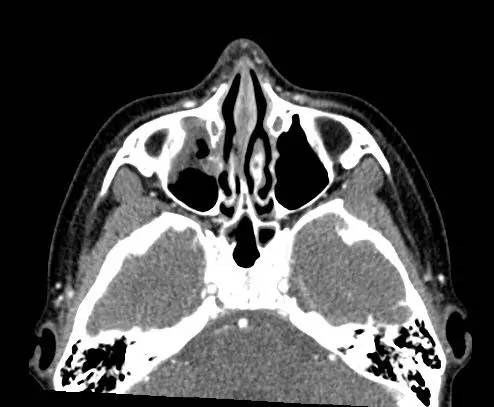

右侧上眼睑软组织肿胀。上眼睑与眼球间可见矩形积气,约1 cmx 0.4 cm x 0.4 cm,并线样影在内穿行。眼球及晶状体正常。眶隔后及眶内软组织无肿胀、血肿或脂肪条纹提示为创伤性。无对比剂外渗。无对急性骨异常。右侧上颌窦粘膜增厚。

【诊断】右上眼睑和眼球间木片存留

There is a piece ofwood between the superior right eyelid and the globe.